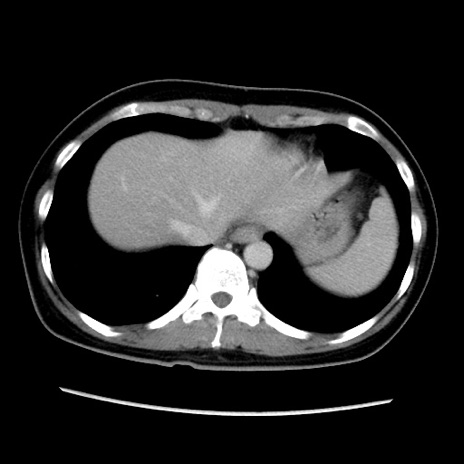

症例39(横断像)

【症例】40歳代女性

【主訴】上下腹部痛

【現病歴】2日目から下腹部痛あり。夜間は痛みで眠れなかった。昨日より上腹部痛と下痢が出現。臥位で痛みは軽快したため、休んでいた。本日になって臥位でも立位でも痛みが強くなってきたため救急要請。

【既往歴】子宮内膜症

【身体所見】部:平坦・軟、左上下腹部に圧痛あり、反跳痛あり。

【データ】WBC 21800、CRP 26.78